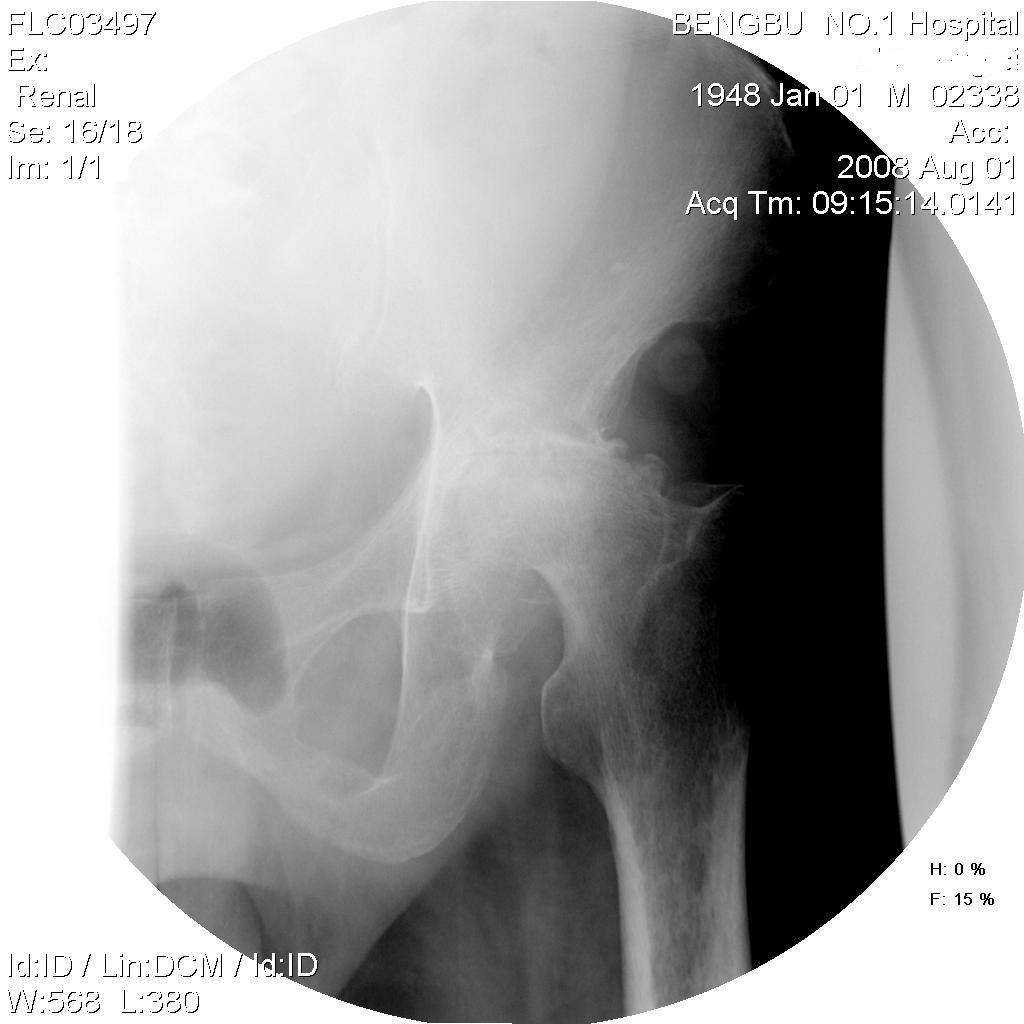

标题: X4652:左股骨头病变,请分析。

男,60岁,左髋部疼痛半年余,近期加重不能行走,爱喝酒。

左股骨头持重面明显塌陷变形,局部示骨质密度不均,可见碎裂、低密度坏死及增生硬化,股骨头向外上方脱位,沈通氏线明显不连续,髋关节间隙明显变窄,关节面边缘增生硬化。首先考虑左股骨头无菌坏死并髋关节半脱位,关节退行性变,先天性髋关节半脱位待排。